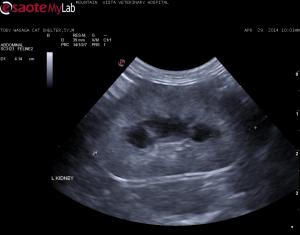

– 5 year old shelter adopted cat severe azotemia, anemia, Feleuk/FIV negative, corono virus positive (I know not helpful)

– no history of toxin ingestion

– thick, hyperechoic renal cortices – no lymphadenopathy and rest of scan unremarkable

lymphoma, FIP, chronic nephritis?

– patient will likely be euthanized due to clinical status but would you FNA these kidneys?

Thick cortices, irregular

Thick cortices, irregular C/M junction, swollen contour of your 3 diffs “lymphoma, FIP, chronic nephritis” I put chronic intersitial nephrosis first and dry FIP second lymphoma distant third just to put a third one in there as the contour and cm structure is still holding more consistent with chronicicity and inflammatory disease and less so with neoplasia. Uniform parenchymal remodeling and expansion is happening. Lymphoma distorts structure, inflammatory fills the sack and remodels if that makes sense. There is a medullary rim sign which FIP can do. Needs core Bx pre or post portem. FNA will rule out lsa and may give insight to granulomatous for FIP but rarely definitive dx on fna but as i find new and select cytologists this may change.

see the renal lymohoma in the sonopath search